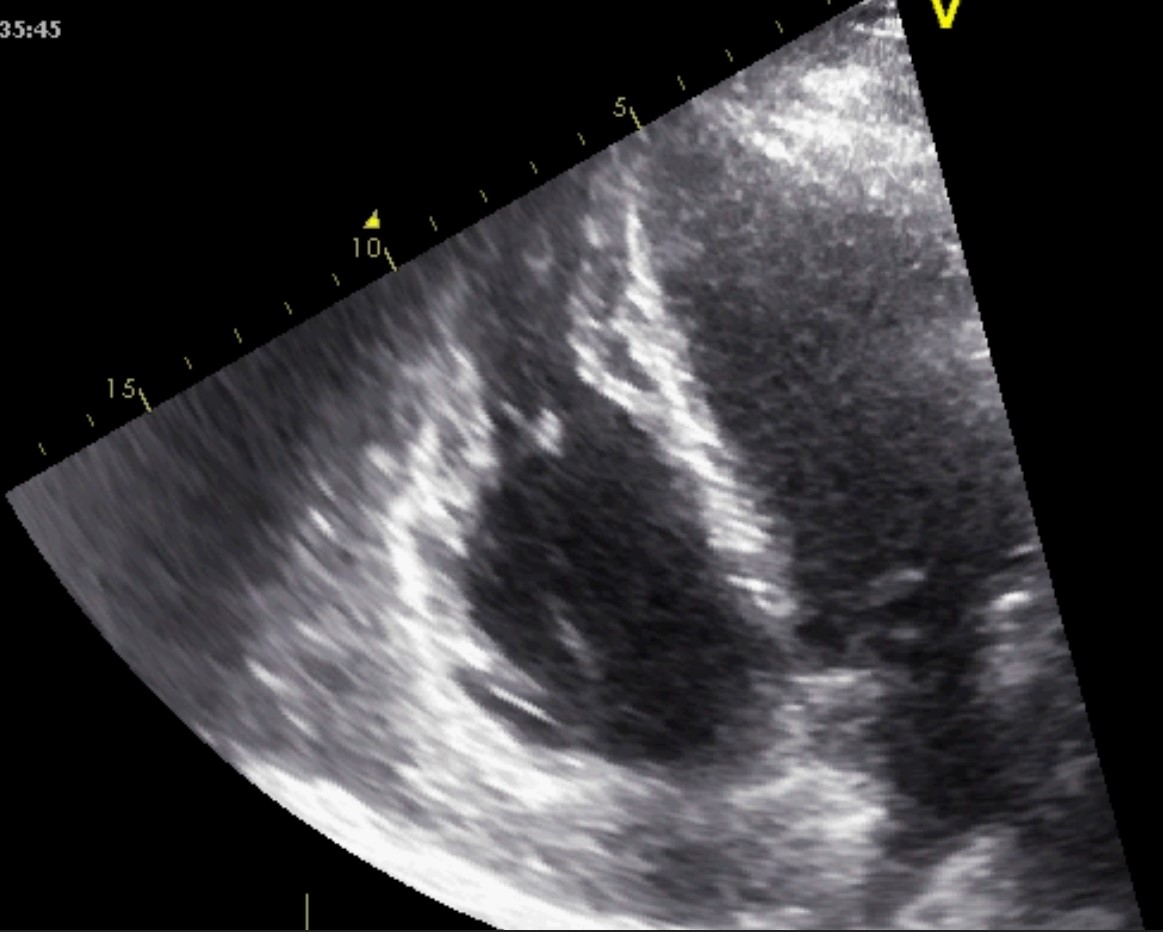

Left ventricular non-compaction cardiomyopathy (LVNC) is characterized by an LV

wall with prominent trabeculae and deep intertrabecular recesses filled with

blood resulting in two layers of myocardium: a thickened noncompacted endocardial

layer and an external, subepicardial thin compacted layer. The diagnosis of LVNC

is obtained through morphologic criteria on transthoracic echocardiography (Fig. 12 and Appendix Video 7). The echocardiographic appearance of isolated LVNC is very

heterogeneous and it can include dilated, hypertrophic or restrictive types. The

Jenni criteria for echocardiographic diagnosis of LVNC are the validated imaging

benchmark [67]. The necessary parameters are assessed using the parasternal

short-axis view at the base, midventricular, and apical levels, and for a

positive diagnosis all four of the following criteria must be met: (1) two

myocardial layers: a thin compacted exterior (epicardial) and a markedly

thickened endocardial layer with several prominent trabeculations and deep

recesses with a maximum ratio of noncompacted to compacted myocardium greater

than 2:1 at end-systole in the parasternal short-axis view; (2) evidence of flow

within the deep intertrabecular recesses through color Doppler; (3) presence of

prominent trabecular meshwork in the LV apex or midventricular segments of the

inferior and lateral wall; (4) maximal systolic compact thickness of